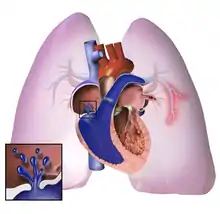

The pathogenesis of pulmonary arterial hypertension (WHO Group I) involves the narrowing of blood vessels connected to and within the lungs. This makes it harder for the heart to pump blood through the lungs, as it is much harder to make water flow through a narrow pipe as opposed to a wide one. Over time, the affected blood vessels become stiffer and thicker, in a process known as fibrosis. The mechanisms involved in this narrowing process include vasoconstriction, thrombosis, and vascular remodeling (excessive cellular proliferation, fibrosis, and reduced apoptosis/programmed cell death in the vessel walls, caused by inflammation, disordered metabolism and dysregulation of certain growth factors).[26][27] This further increases the blood pressure within the lungs and impairs their blood flow. In common with other types of pulmonary hypertension, these changes result in an increased workload for the right side of the heart.[15][28] The right ventricle is normally part of a low pressure system, with systolic ventricular pressures that are lower than those that the left ventricle normally encounters. As such, the right ventricle cannot cope as well with higher pressures, and although right ventricular adaptations (hypertrophy and increased contractility of the heart muscle) initially help to preserve stroke volume, ultimately these compensatory mechanisms are insufficient; the right ventricular muscle cannot get enough oxygen to meet its needs and right heart failure follows.[15][27][28] As the blood flowing through the lungs decreases, the left side of the heart receives less blood. This blood may also carry less oxygen than normal. Therefore, it becomes harder and harder for the left side of the heart to supply sufficient oxygen to the rest of the body, especially during physical activity.[29][30][10] During the end-systolic volume phase of the cardiac cycle, the Gaussian curvature and the mean curvature of right ventricular endocardial wall of PH patients was found to be significantly different as compared to controls.[31]

Pathogenesis in pulmonary hypertension due to left heart disease (WHO Group II) is completely different in that constriction or damage to the pulmonary blood vessels is not the issue. Instead, the left heart fails to pump blood efficiently, leading to pooling of blood in the lungs and back pressure within the pulmonary system. This causes pulmonary edema and pleural effusions.[33] In the absence of pulmonary blood vessel narrowing, the increased back pressure is described as 'isolated post-capillary pulmonary hypertension' (older terms include 'passive' or 'proportionate' pulmonary hypertension or 'pulmonary venous hypertension'). However, in some patients, the raised pressure in the pulmonary vessels triggers a superimposed component of vessel narrowing, which further increases the workload of the right side of the heart. This is referred to as 'post-capillary pulmonary hypertension with a pre-capillary component' or 'combined post-capillary and pre-capillary pulmonary hypertension' (older terms include 'reactive' or 'out-of-proportion' pulmonary hypertension).[12][17][34]